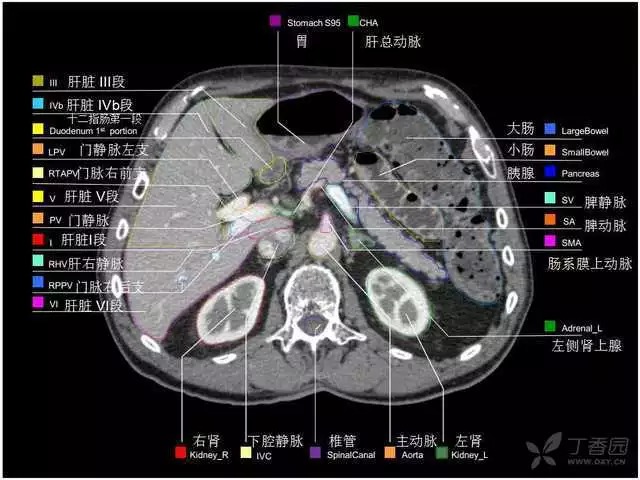

腹部肝脏高清CT断层的图谱

全腹部高清CT图谱,淋巴结彩色图谱,血管解剖图谱大汇总!

肝段,肝内管道的分布规律